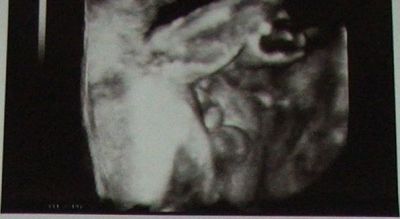

Kép Kép Kép

Ő a mi kisfiunk,itt 28 hetesek voltunk!

Igen Ági az amire gondolsz!!!! :D